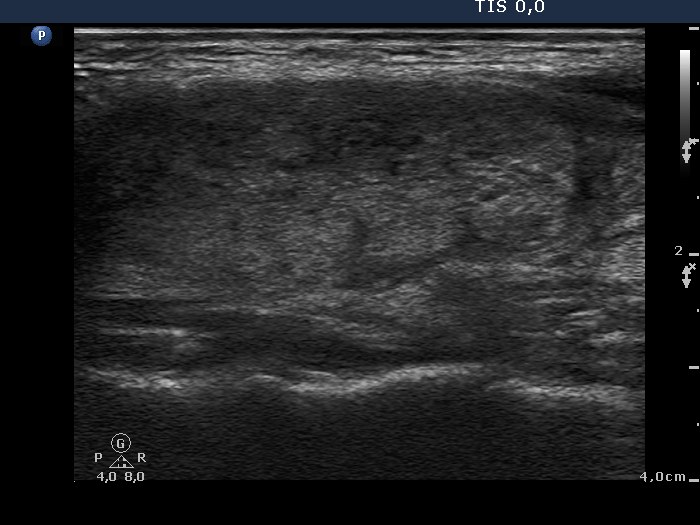

Subacute granulomatous thyroiditis - case 370 (ultrasonographic picture 5)

Left lobe, longitudinal view.